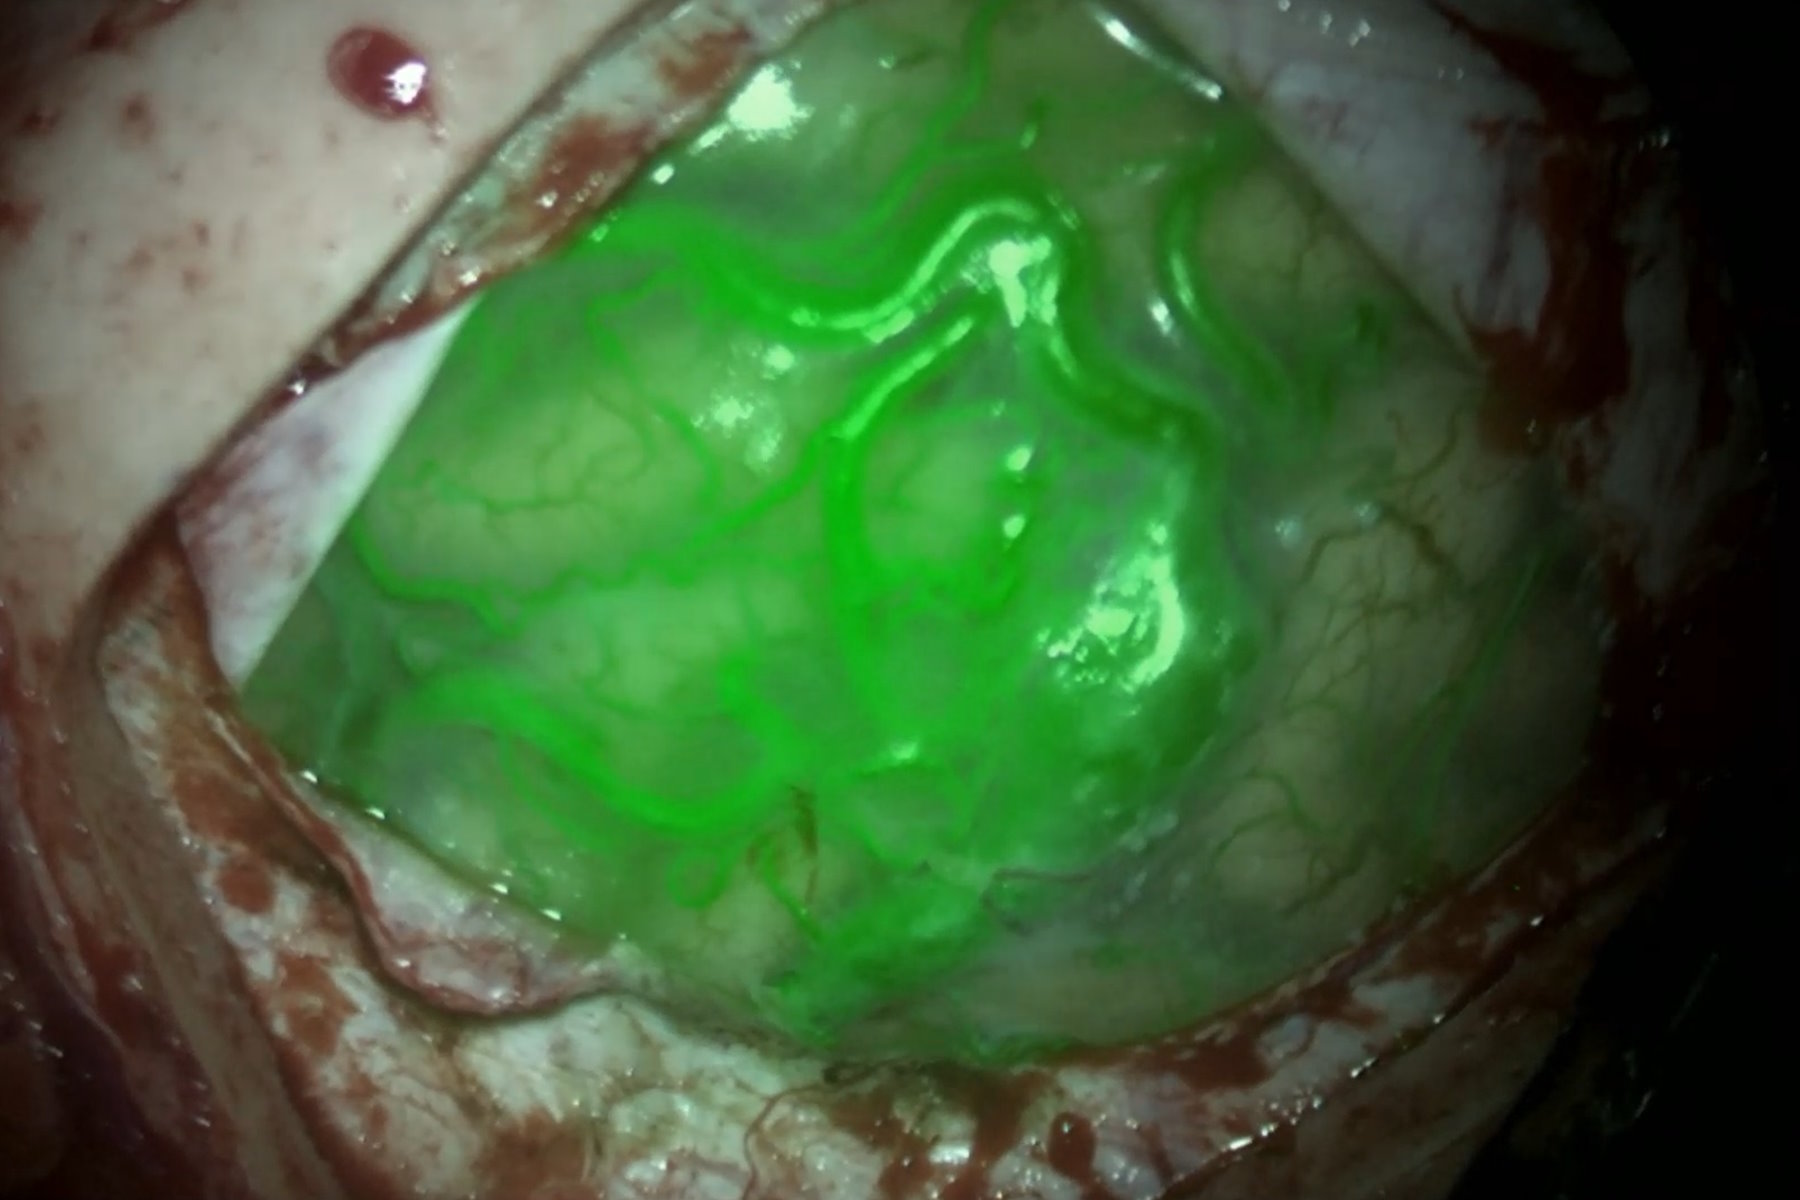

Use of GLOW800 Augmented Reality during AVM surgery. Image courtesy of Prof. Philippe Bijlenga. Use_of_GLOW800_Augmented_Reality_during_AVM_surgery.jpg

For AVM surgery, Prof. Bijlenga explains, the first step is to understand the AVM, studying the draining vein and ectasies, the en passant arteries, the arterial feeders and the relation of the tip and the ventricle. Augmented Reality allows us to customize the craniotomy and identify quickly the feeders from the en passant vessels. It also helps follow the AVM dissection plan by showing the contours. The use of GLOW800 Augmented Reality during the resection allows to visualize the blood flow and timing, with the FL800 mode providing confirmation that there is no remnant. A 3D angiogram is also performed is some cases.

GLOW800 Augmented Reality is a valuable tool to see which vessels are perfused and how fast vessels are perfused. In deep seated surgeries and for small vessels, the complementary use of the FL800 mode is recommended.